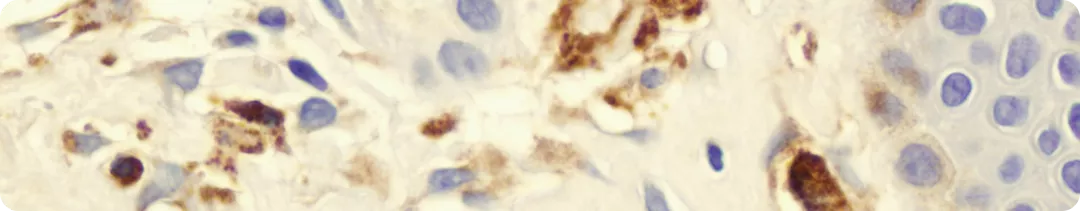

морфологическое исследование КМ для выявления инфильтратов и морфологии ТК;

иммуногистохимическое исследование КМ (экспрессия CD117, CD25 и/или CD2) для выявления неопластических ТК.